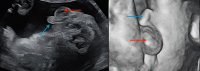

A 46,XX male represents a variant of Klinefelter syndrome (47,XXY), under the category of a disorder of sex development (DSD). Despite possessing an XX karyotype, these individuals exhibit a male phenotype, which, in this case, results from a translocation of the SRY gene from the Y chromosome onto the X chromosome. This genetic alteration results in the development of male gonadal characteristics. This case report outlines a prenatal diagnosis of a 46,XX female in conflict with a level 2 ultrasound. It details the patient's presentation, diagnosis of an SRY-positive 46,XX male, and medical history. The discussion focuses on the advantages of early identification and intervention in managing symptom progression and addressing fertility challenges through hormone replacement therapy. Further exploration of 46,XX DSD early detection and the underlying mechanisms is essential for refining diagnostic and therapeutic approaches that result in a greater quality of life for these patients.